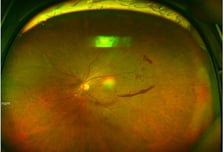

흐릿한 눈 앞, 나이 탓만 했다간...'조용한 실명' 다가온다

나이가 들면서 시력이 떨어질 때 단순한 노화로 여기고 넘기는 경우가 적잖다. 하지만 의외로 '망막'에 병이 생긴 경우가 많다. 망막은 눈의 가장 안쪽에서 빛을 감지하고 시각 정보를 뇌로 전달하는 신경조직으로, 이 부위에 손상이 생기면 중심 시야가 흐려지거나 시야 일부가 가려지는 등 심한 경우 실명으로 이어질 수 있다. 대표 질환으로는 △당뇨망막병증 △망막박리 △망막혈관폐쇄 △황반변성 등이 있다. 초기 자각 증상이 거의 없어 병이 상당히 진행된 뒤에 발견되는 경우가 많아 주의가 필요하다. 강동경희대병원 안과 김유진 교수의 도움말로, 망막질환의 증상과 치료법에 대해 알아본다. ━당뇨망막병증…당뇨병 있으면서 시야 흐릴 때━당뇨망막병증은 당뇨병으로 인해 망막 미세혈관이 손상되면서 발생한다. 초기에는 증상을 느끼지 못하는 경우가 많으며, 질환이 이미 진행하였을 때 증상이 나타나기 시작한다. 초기 증상으로는 시야가 흐리게 보이거나, 시야에 검은 점(비문증)이 나타날 수 있다. 병이 점차 진행되면 출혈·부종이 발생하며, 산소 부족으로 인해 망막에 비정상적인 혈관(신생혈관)이 자라나 심한 시력 저하나 실명을 초래할 수 있다.